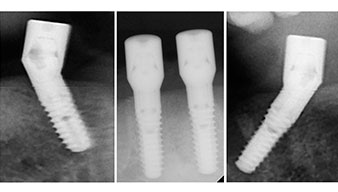

A three-dimensional cone beam computed tomography scan (CBCT, Planmeca) was performed to aid planning and minimize risks. This revealed that the quality and quantity of the available bone were sufficient for the surgery and immediate restoration using the Fast & Fixed method. Following the protocol for this concept, the implants are inserted at 35, 32, 42 and 45. Angling the distal implants by up to 45° shifts the emergence profile to posterior and generates a larger support polygon (Fig. 3).

The surgical protocol for the implants employed (SKY, bredent medical) specifies a speed of 1,200 rpm for the pilot drilling (Fig. 7 - 9).

This corresponds to the next preset position in the Implantmed. Here we see the W&H contra-angle handpiece being held at a 45° angle to mesiocaudal in the region of 45 in order to preserve the mental nerve. The mental foramen is used as the anatomic reference for all drilling in this region. The subsequent holes were drilled at a reduced speed of 300 rpm (Fig. 10 and 11).